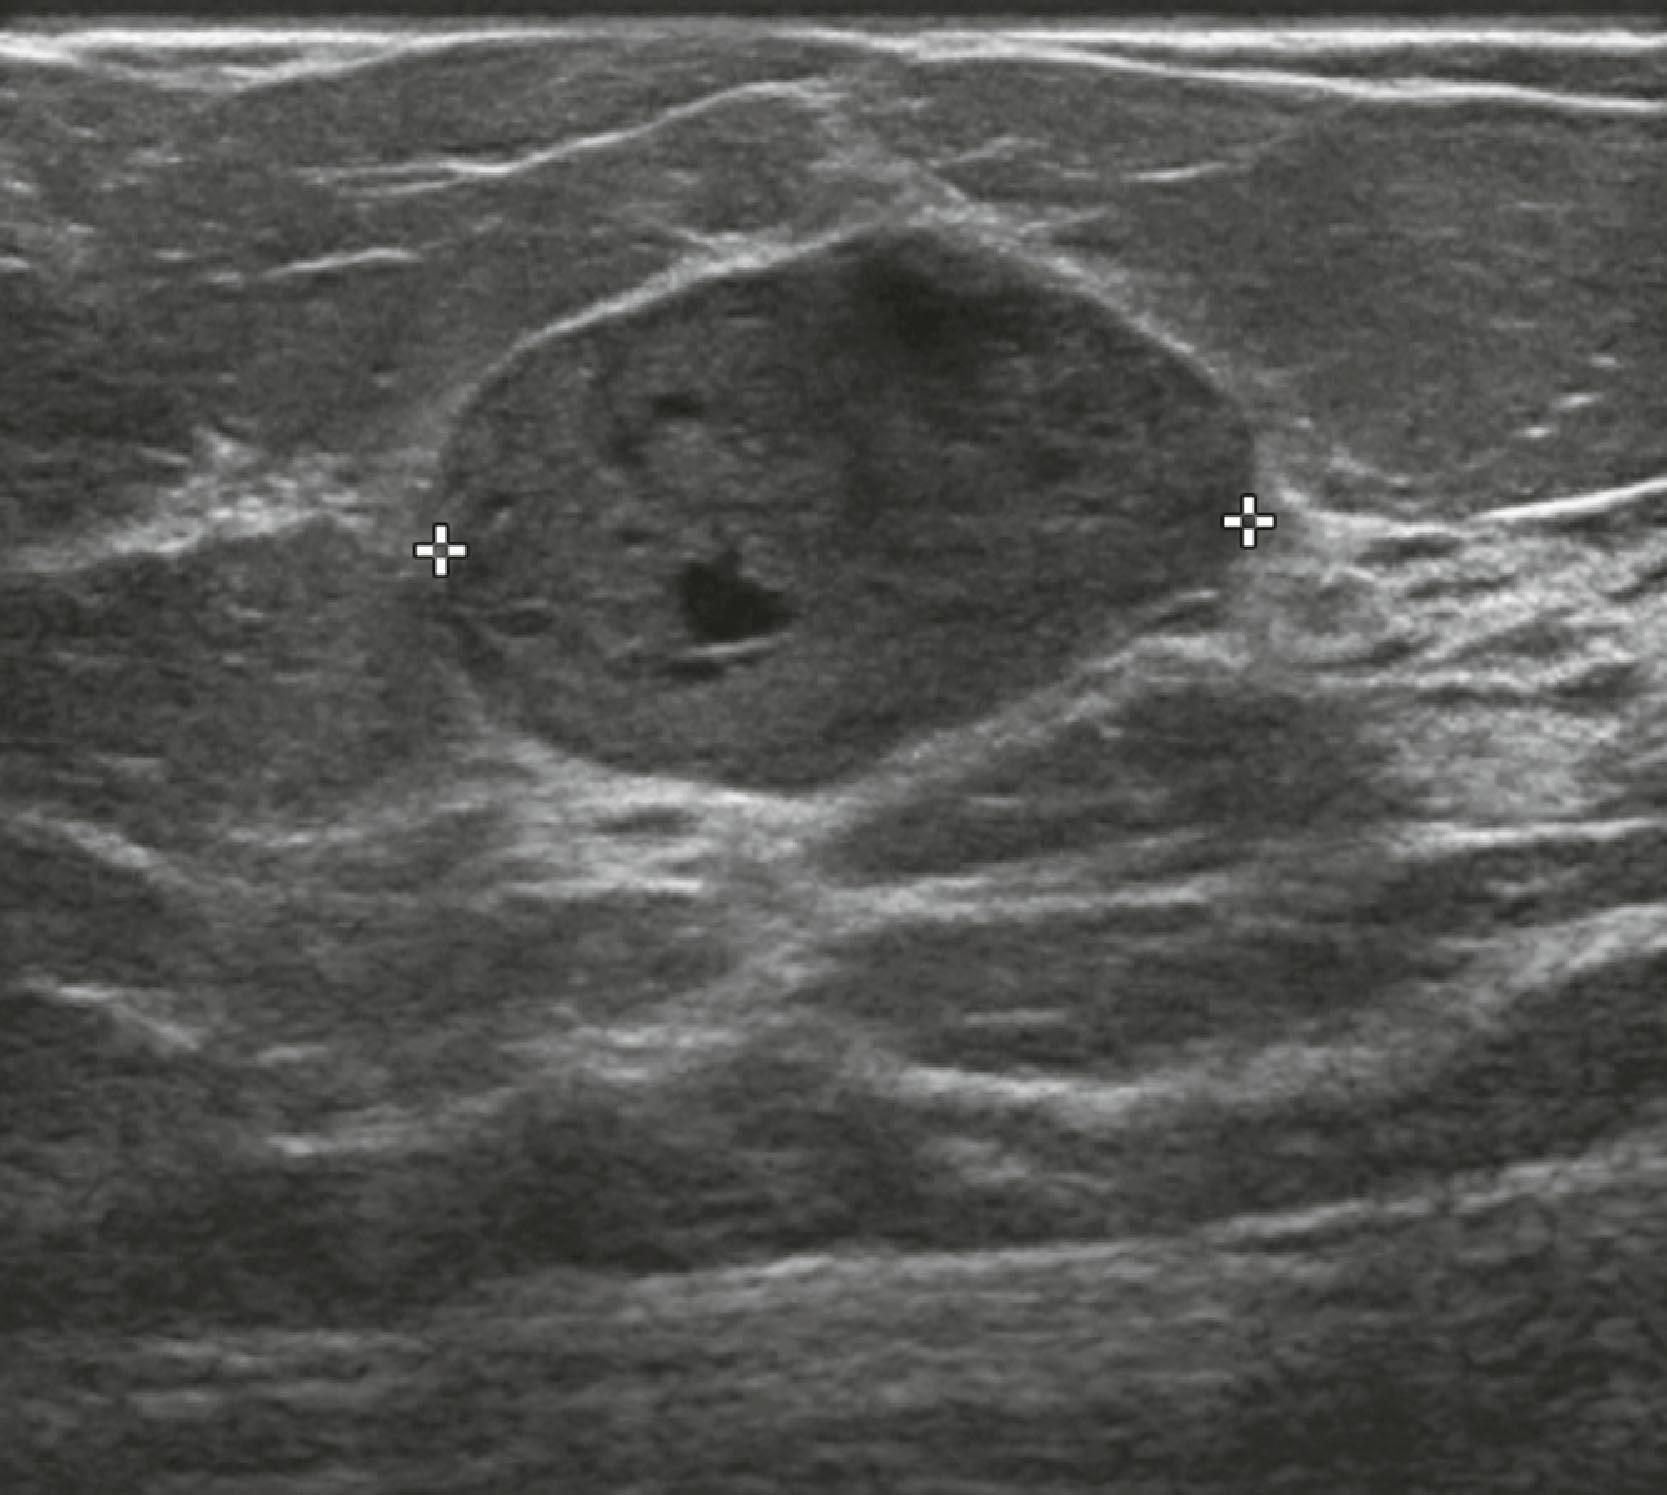

Sonographic features of benign masses, originally reported by Stavros and coworkers, include three or fewer gentle lobulations, orientation parallel to the chest wall, and a thin echogenic pseudocapsule, along with absence of any malignant features. Other features favoring a benign etiology are oval shape, circumscribed borders, and uniform hyperechogenicity ( Fig. 8.15 ). However, many benign-appearing masses undergo percutaneous or excisional biopsy because they are new or enlarging and cannot be unequivocally distinguished from well-circumscribed malignancies ( Fig. 8.16 ). A very large but well-defined mass is suspect for a phyllodes tumor ( Fig. 8.17 ).

Fig. 8.15, A fibroadenoma typically has well-defined margins and an oval shape with three or fewer gentle lobulations.

Fig. 8.16, This 4.5-cm palpable mass has well-defined margins on Right Mediolateral Oblique view (RMLO) on mammography ( A ), but on sonography ( B ), it has inhomogeneous internal echoes and a few microlobulations. Biopsy revealed infiltrating duct carcinoma, nuclear grade 3.